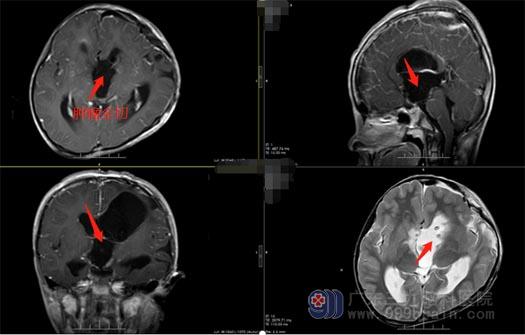

“肿瘤很大,合并有脑积水,嘉嘉的激素水平也很低,手术比较棘手”。为了能最大程度地切除肿瘤,同时又保证患儿的生命安全,鲁明及神经外五科王国良主任都高度重视,带领外五科团队进行病例讨论,一致决定改善基础条件后积极手术治疗。家属也非常积极地配合治疗, 3月17日在全麻下行“鞍上、三脑室巨大占位切除术”,术中显微镜下见肿瘤质地坚硬,血供丰富,分块切除肿瘤,术中视神经、颈内动脉、垂体柄保护完好,手术顺利结束。